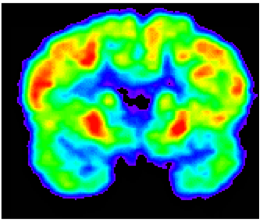

Radioisotopes have a variety of applications in research, industry, and medicine. Research uses of radioisotopes vary widely from tracers in biological systems to development of systems for detecting covert nuclear weapons. Industrial uses include thickness measurement using the transmission of radiation through a material, material flow measurement by injecting radioactive tracers into the flow path, detecting explosives, and electrical power generation using radioisotope thermoelectric generators. Radioisotopes are used in medicine for diagnostic imaging as well as treatment of diseases such as hyperthyroidism and cancer. The Nuclear Engineering Teaching Laboratory can produce a variety of radioisotopes to meet client needs.